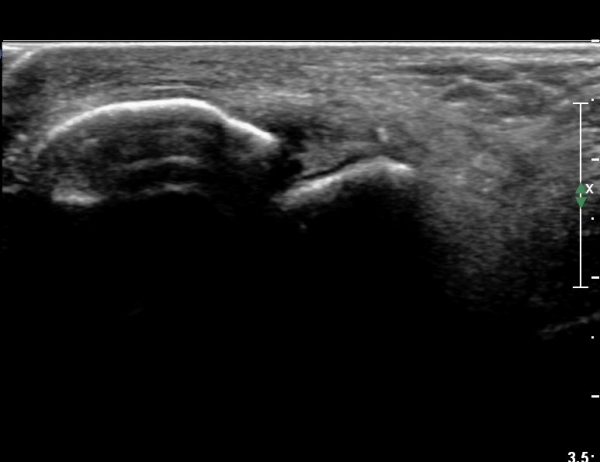

Àü°ÅºñÀδë Á¾´Ü¸é°Ë»ç¿¡¼­  Àü°ÅºñÀδëÀÇ ÆÄ¿­À» º¸ÀÓ(»çÁø 2).